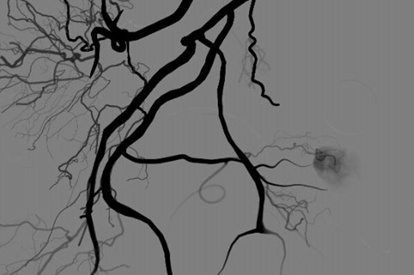

EVAR (Endovascular Aneurysm Repair) Module

TEVAR Module

Advanced TEVAR Module

Endovascular Trauma Management Module

Venous Intervention Module